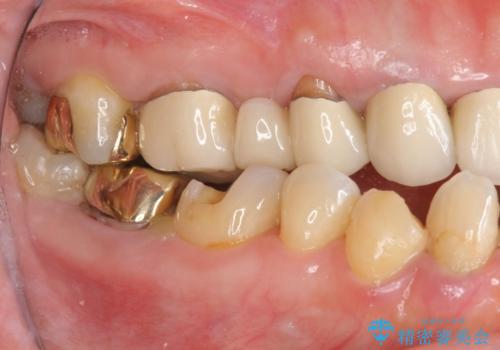

強い咬合力で奥歯がボロボロに インプラント治療による咬合回復と全顎セラミック治療